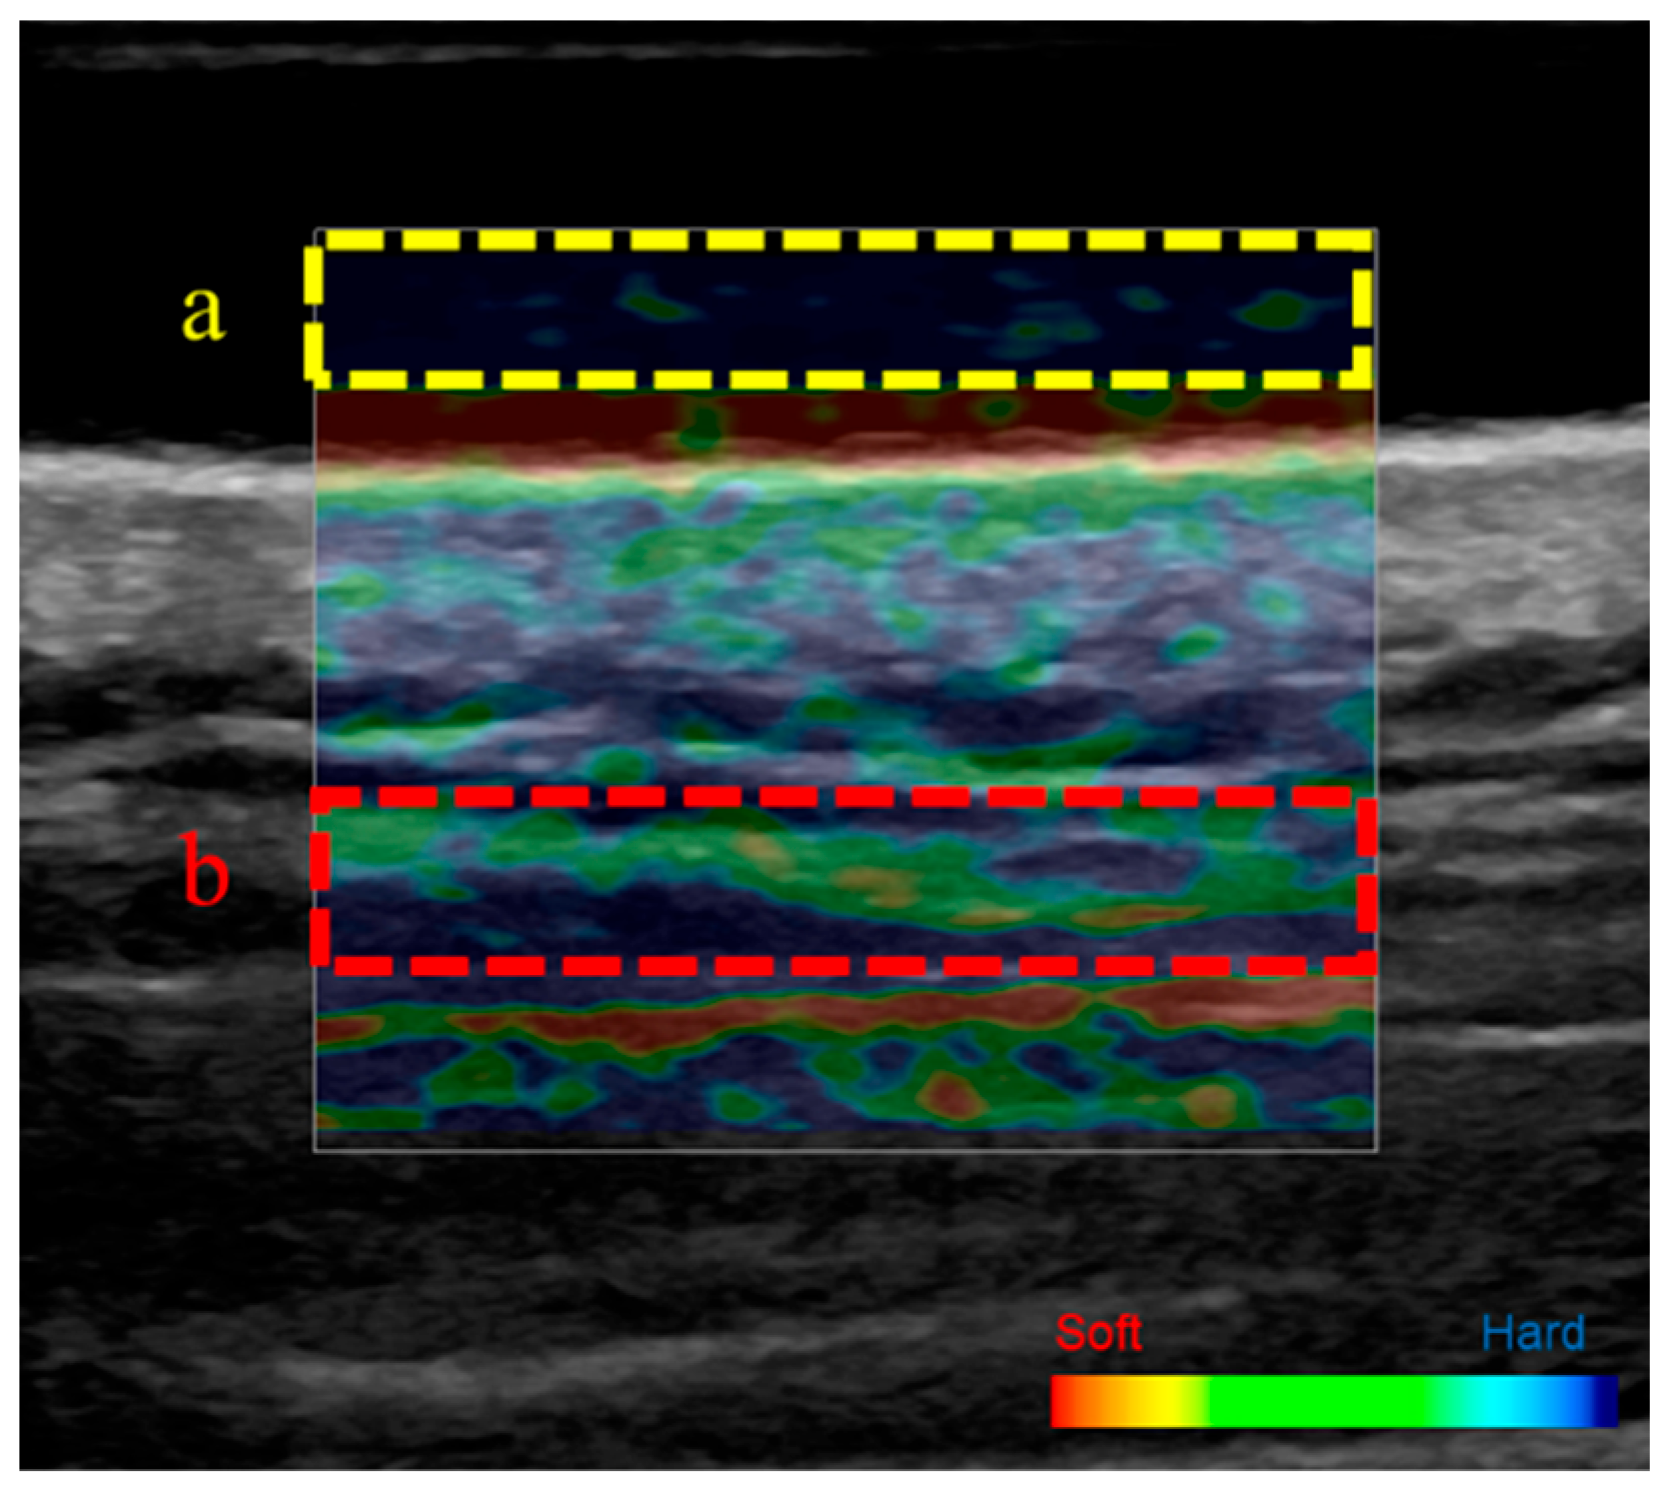

2.5. Ultrasound Strain Elastography